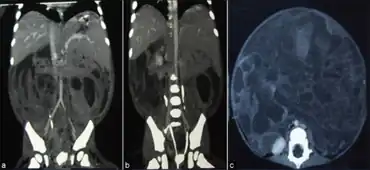

| a-c)Contrast-enhanced computed tomography of abdomen | |